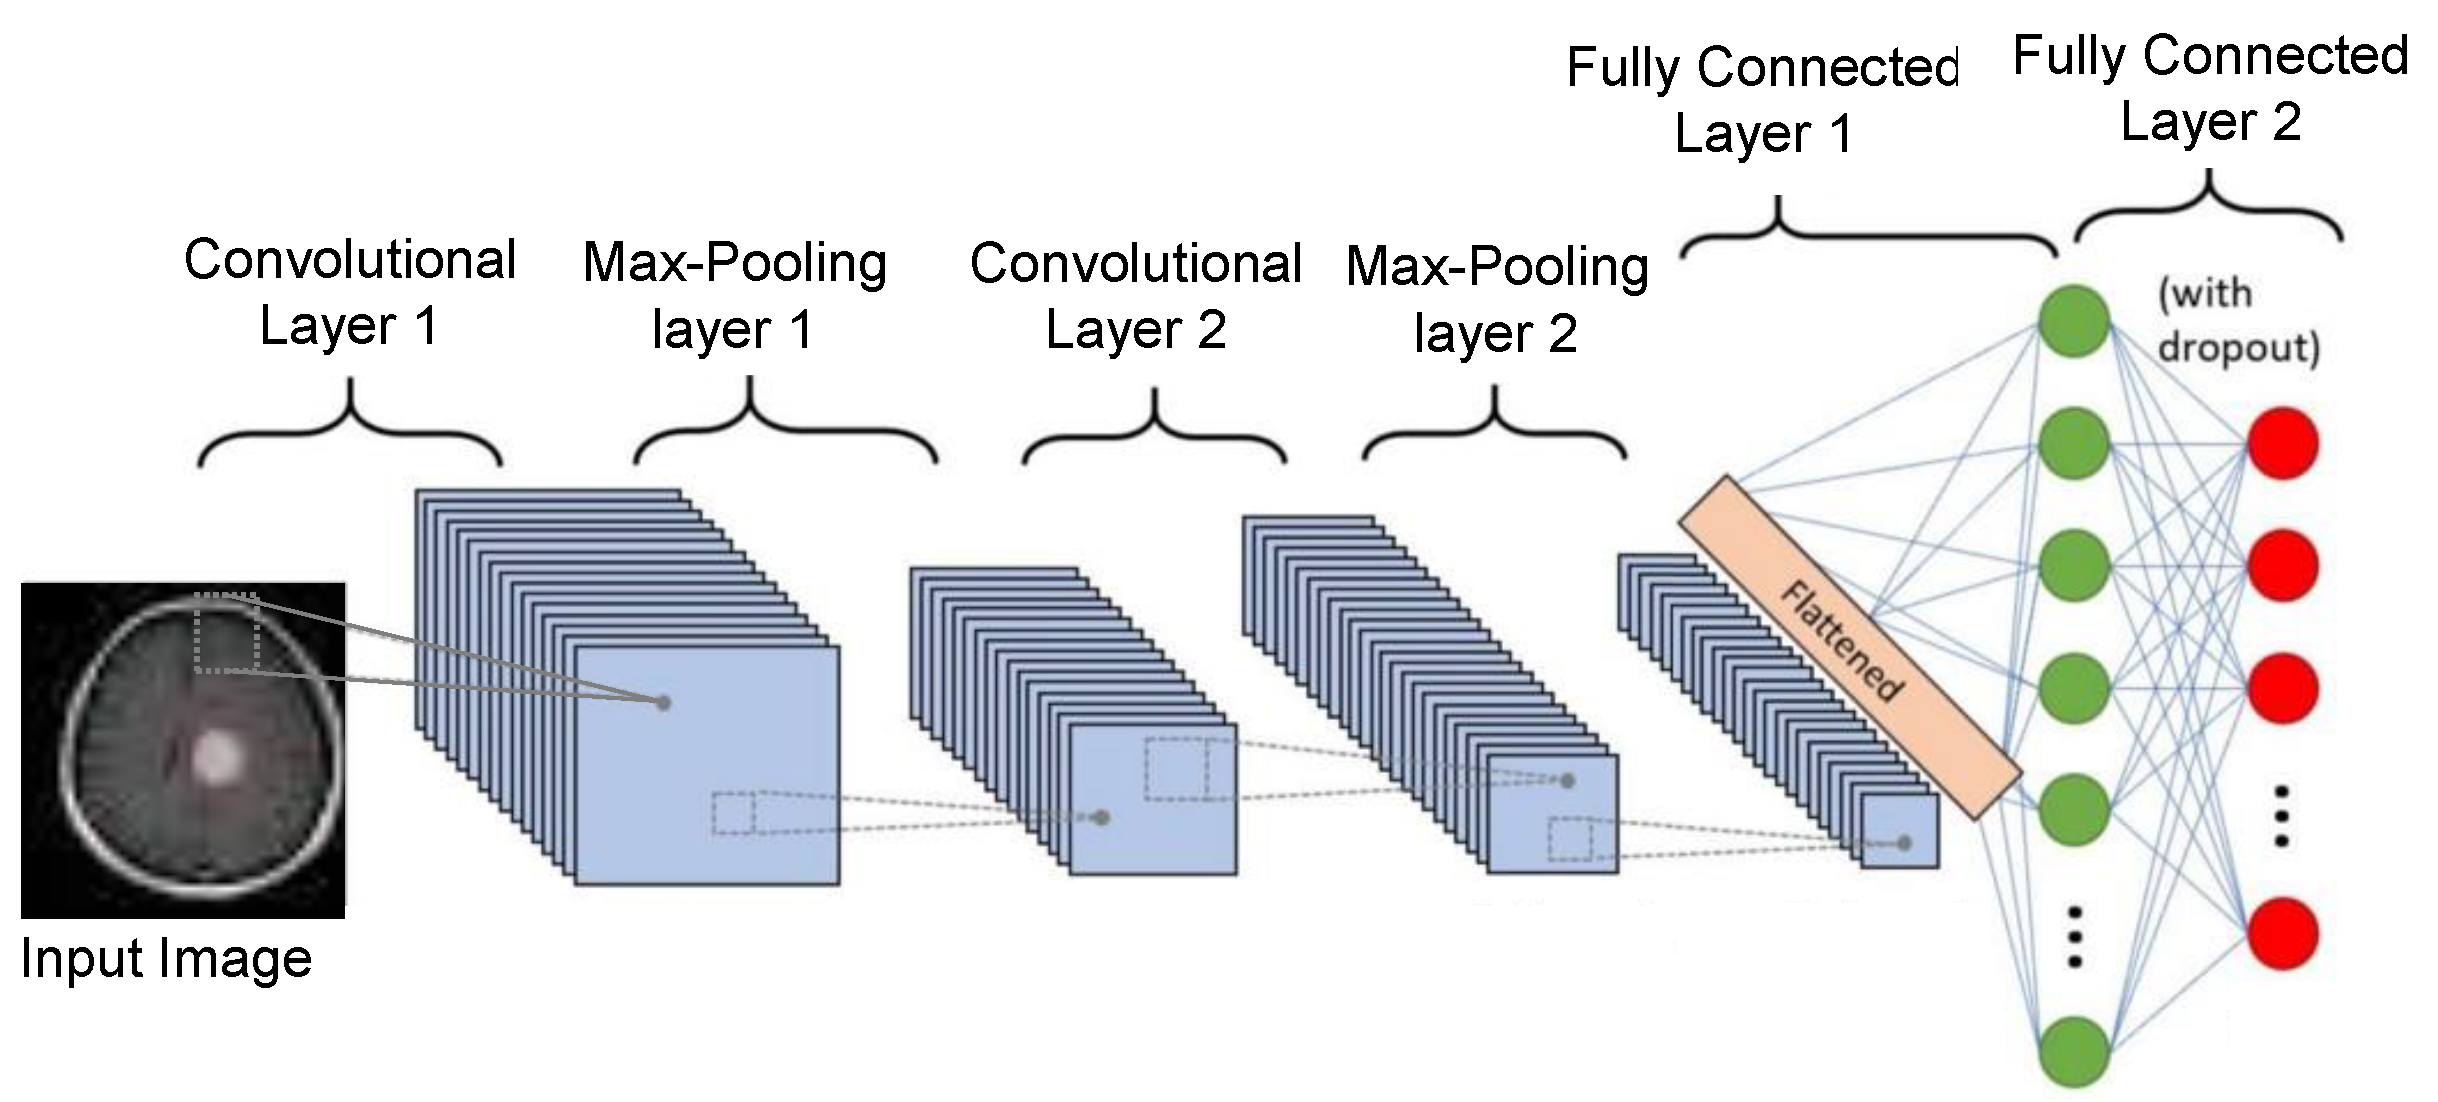

3.1. CNN Feature Extractor